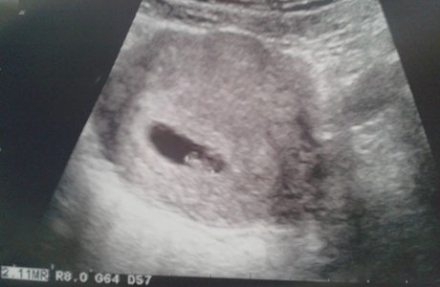

Terhesnapló 6. - „Charlie” angyalai

Ötödik terhesnaplónk Koppány születésével véget ért, bár Csumpi - kis fáziskéséssel - jelentkezni fog még a Babanet oldalain. Most viszont szeretnénk nektek bemutatni Lénát, a Babanet hatodik terhesnaplójának szerzőjét. Léna Skóciában él 2,5... 12 hozzászólás